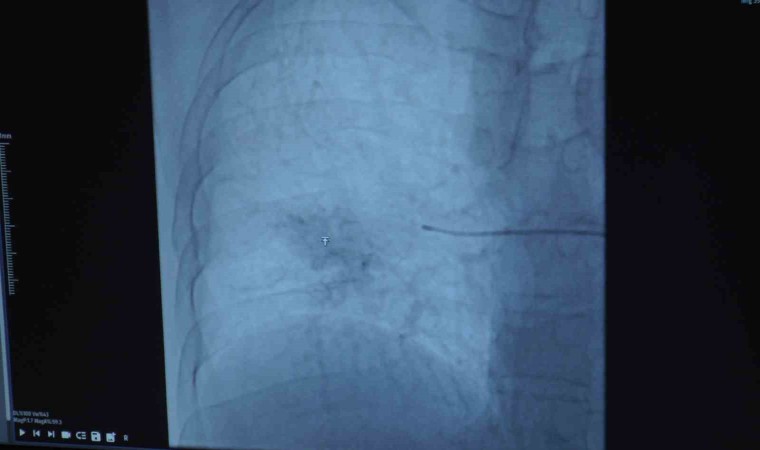

Girişimsel Radyoloji Bölümü’nden Dr. Oğuz Aslan da Behçet hastalığı olanların kanama durumunda akciğer atardamarlarında bir anevrizma olabileceğini akıllarında bulundurması gerektiğini söyleyerek, “Osman bey bize göğüs hastalıkları tarafından yönlendirildi. Kendisinin Behçet hastalığı tanılı, tekrarlayan akciğer kaynaklı kanamaları mevcuttu ve pulmoner anevrizma dediğimiz bir baloncuk mevcuttu Behçet hastalığında sekonder olarak nadir gelişen bir durum olarak. Hastamıza bu anevrizmanın kapatılabileceğini ve işlemin nasıl olduğunu, risklerini anlattık. Kendisi de düşündü ve tedavi olmaya karar verdi. Öylelikle bir teşhise dair anjiyoya aldık kendisini. Tedavi planımızı belirledik ve ikinci bir seansta kendisine bu büyük damarları tıkamakta kullandığımız vasküler tıkaçlar dediğimiz materyaller ile anevrizmasını kapattık. Anevrizma kapatmanın aslında birçok yöntemi var ama hastamızın besleyici damarı çok büyük olduğu için bunları daha büyük damarları tıkamak için kullandığımız materyalleri kullandık. Bir gün serviste yattı ve ertesi gün taburculuğunu sağlamış olduk. Bizim gördüğümüz hastaların çoğu Behçet hastası ve bu hastaların yüzde 1-2’sinde görülebiliyor bu komplikasyon. Embolizasyon işlemi sonrasında hastamızın bu mevcut durumu tamamen kapandığı için en azından bu anevrizma özelinde ekstra bir akciğer kanaması hemoptizi ihtimali ortadan kalkmış oldu. Şöyle söyleyebiliriz; Behçet hastalığı tanısı olan hastaların öksürükle ağzından kan gelmesi durumunda akciğer atardamarında bir anevrizma olabileceği akılda bulundurulmalı ve bunun tedavisi için gerekli başvurular da yapılmalıdır. Burada hastalar Girişimsel Radyoloji Kliniği’ne de başvurabilirler ya da göğüs hastalıkları tarafından da bize yönlendirilebilirler” ifadelerini kullandı.